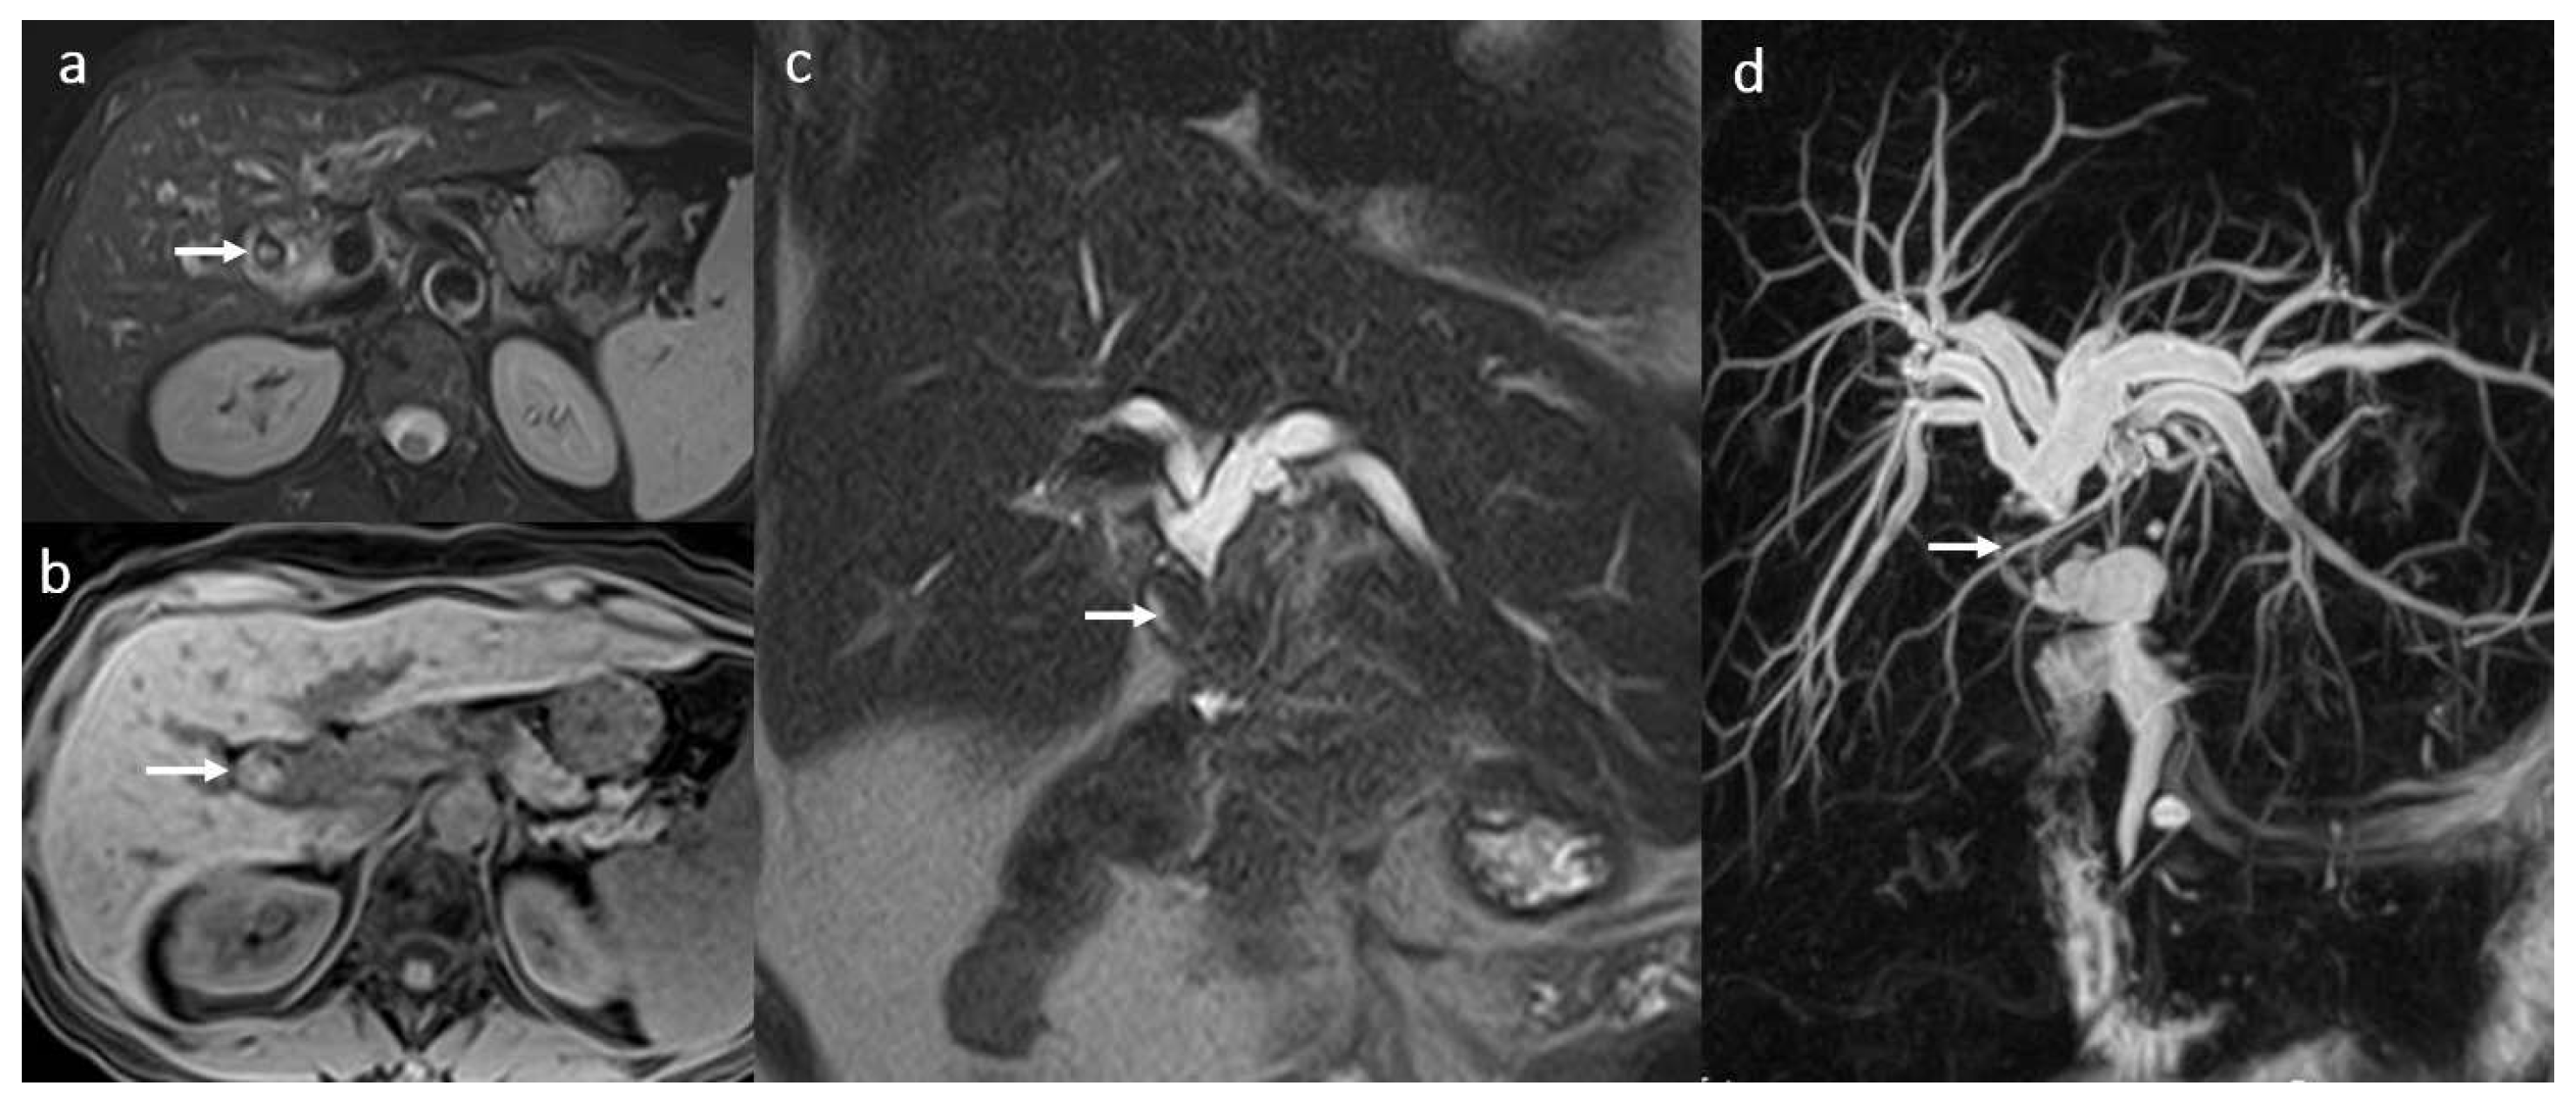

3.5. Biloma and Bile Leaks

3.6. Secondary Cholangitis